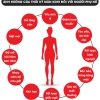

Những nguy hiểm chính của sốt xuất huyết:

1. Sốc sốt xuất huyết (sốc Dengue)

2. Xuất huyết nặng

3. Tràn dịch màng phổi, dịch ổ bụng

4. Tổn thương gan

5. Suy thận, suy tim, suy đa cơ quan

Dấu hiệu cảnh báo cần đi viện ngay